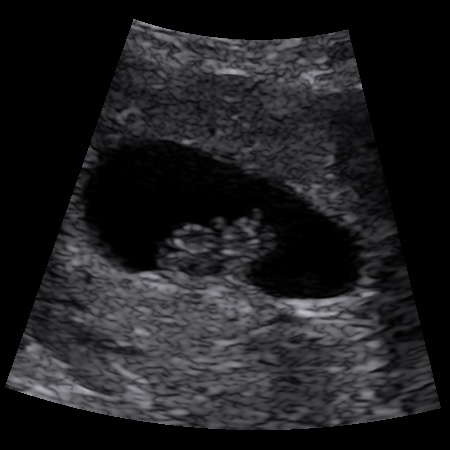

Oh and to interpret the scan pic, apparently it's the head on the left and the bum up in the air Hmm